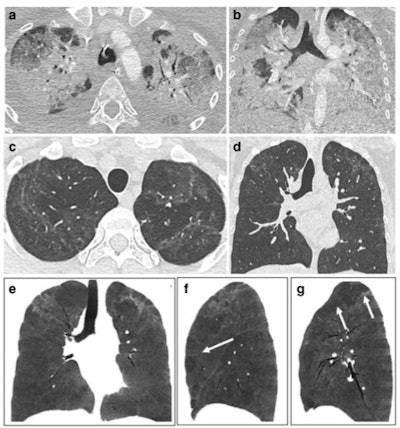

- Post-COVID-19 pneumonia changes are mainly consistent with prior organizing pneumonia and are likely to disappear within 12 months of recovery from the acute infection in the majority of patients.

- At present, with the longest series of follow-up examinations reported not exceeding 12 months, the development of persistent or progressive fibrosis in at least some individuals cannot yet be excluded.

- Residual ground glass opacification may be associated with persisting bronchial dilatation and distortion and might be termed "fibrotic-like changes" probably consistent with prior organizing pneumonia.

The report devotes a section to the role of CT pulmonary angiography (CTPA) and dual-energy CT (DECT). DECT enables assessment of pulmonary perfusion and the detection of capillary microvascular thrombosis.

"If validated in larger series, DECT might be used in patients with persisting abnormal gas exchange despite apparent normalization of lung parenchyma on CT," the authors wrote. "To date, there is no evidence in the literature that macrovascular disease plays a role in long COVID or post-COVID syndrome."